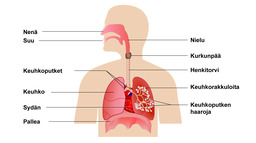

Ilman kulku keuhkorakkuloihin.

Hengityselimistö

Sisäänhengityksessä ilmaa kulkeutuu keuhkoihin, ja uloshengityksessä ilma poistuu keuhkoista ulos.

Sisäänhengityksessä ilmaa kulkeutuu keuhkoihin, ja uloshengityksessä ilma poistuu keuhkoista ulos.Ilma kulkeutuu joko nenän tai suun kautta henkitorveen, jonka voit tuntea sormilla kaulasi etuosassa. Henkitorvi haarautuu kahdeksi keuhkoputkeksi, jotka päätyvät keuhkoihin. Keuhkot rakentuvat pienistä palleroista, keuhkorakkuloista.